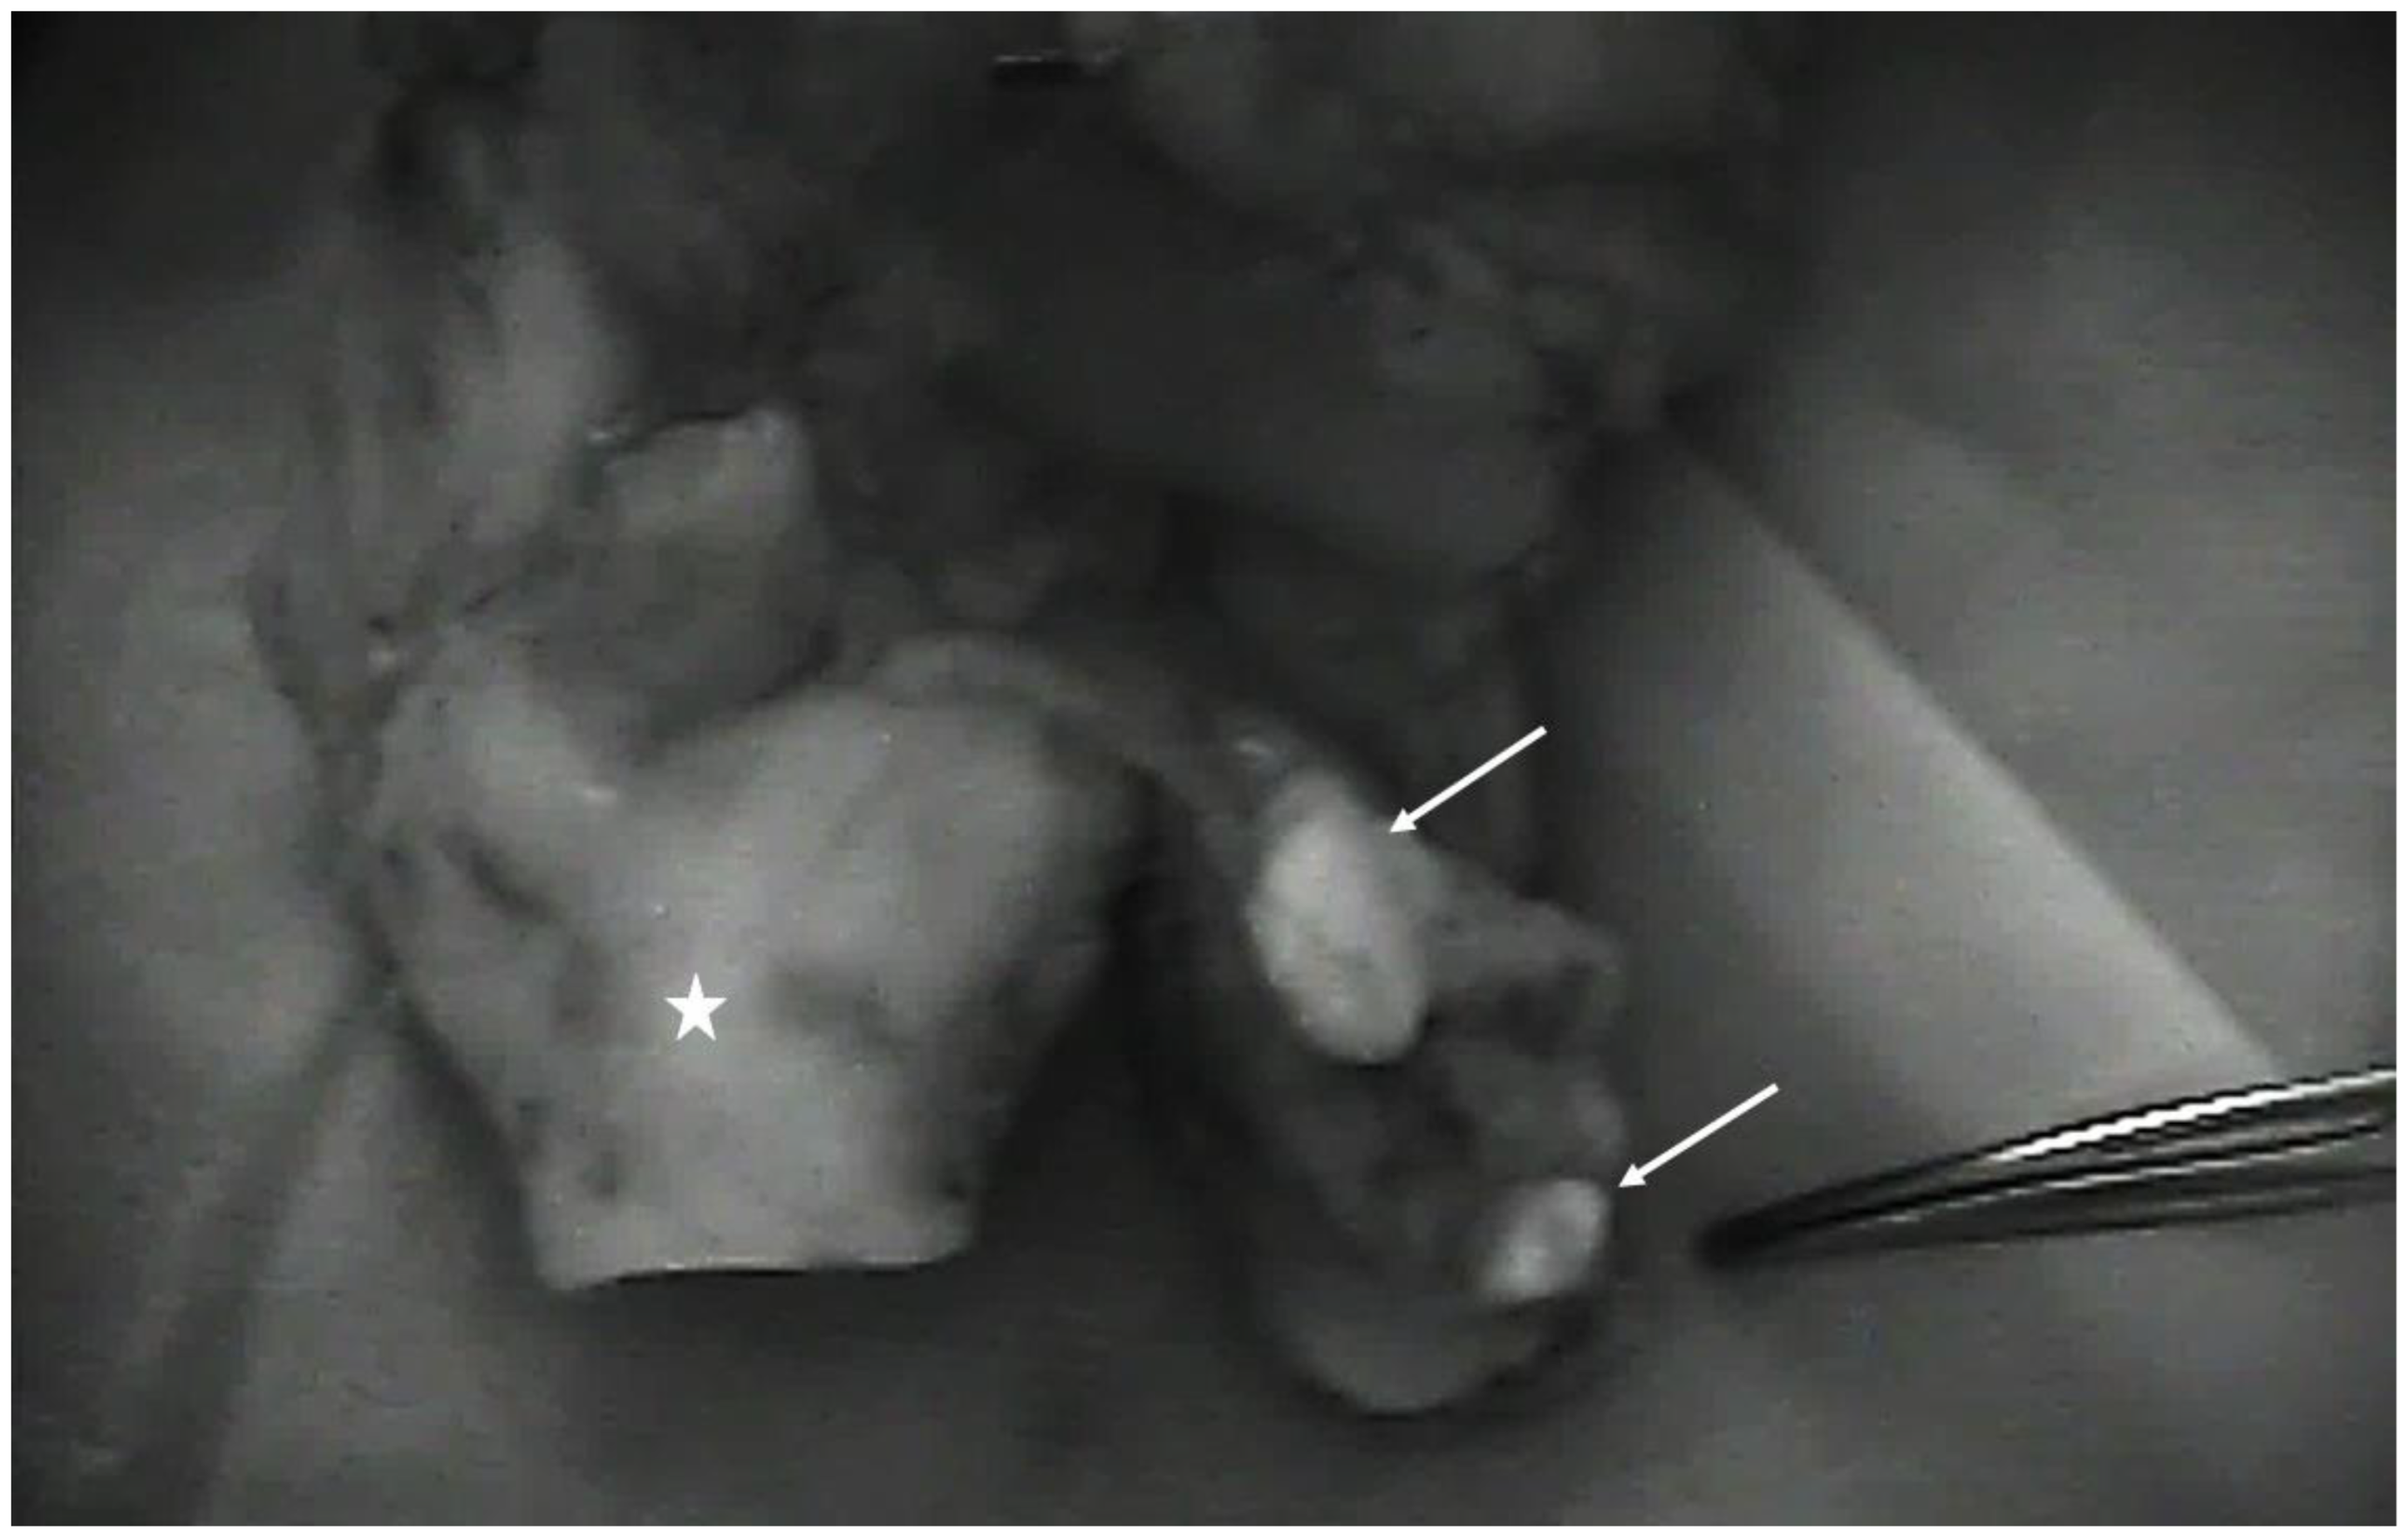

2.1. Surgical Technique